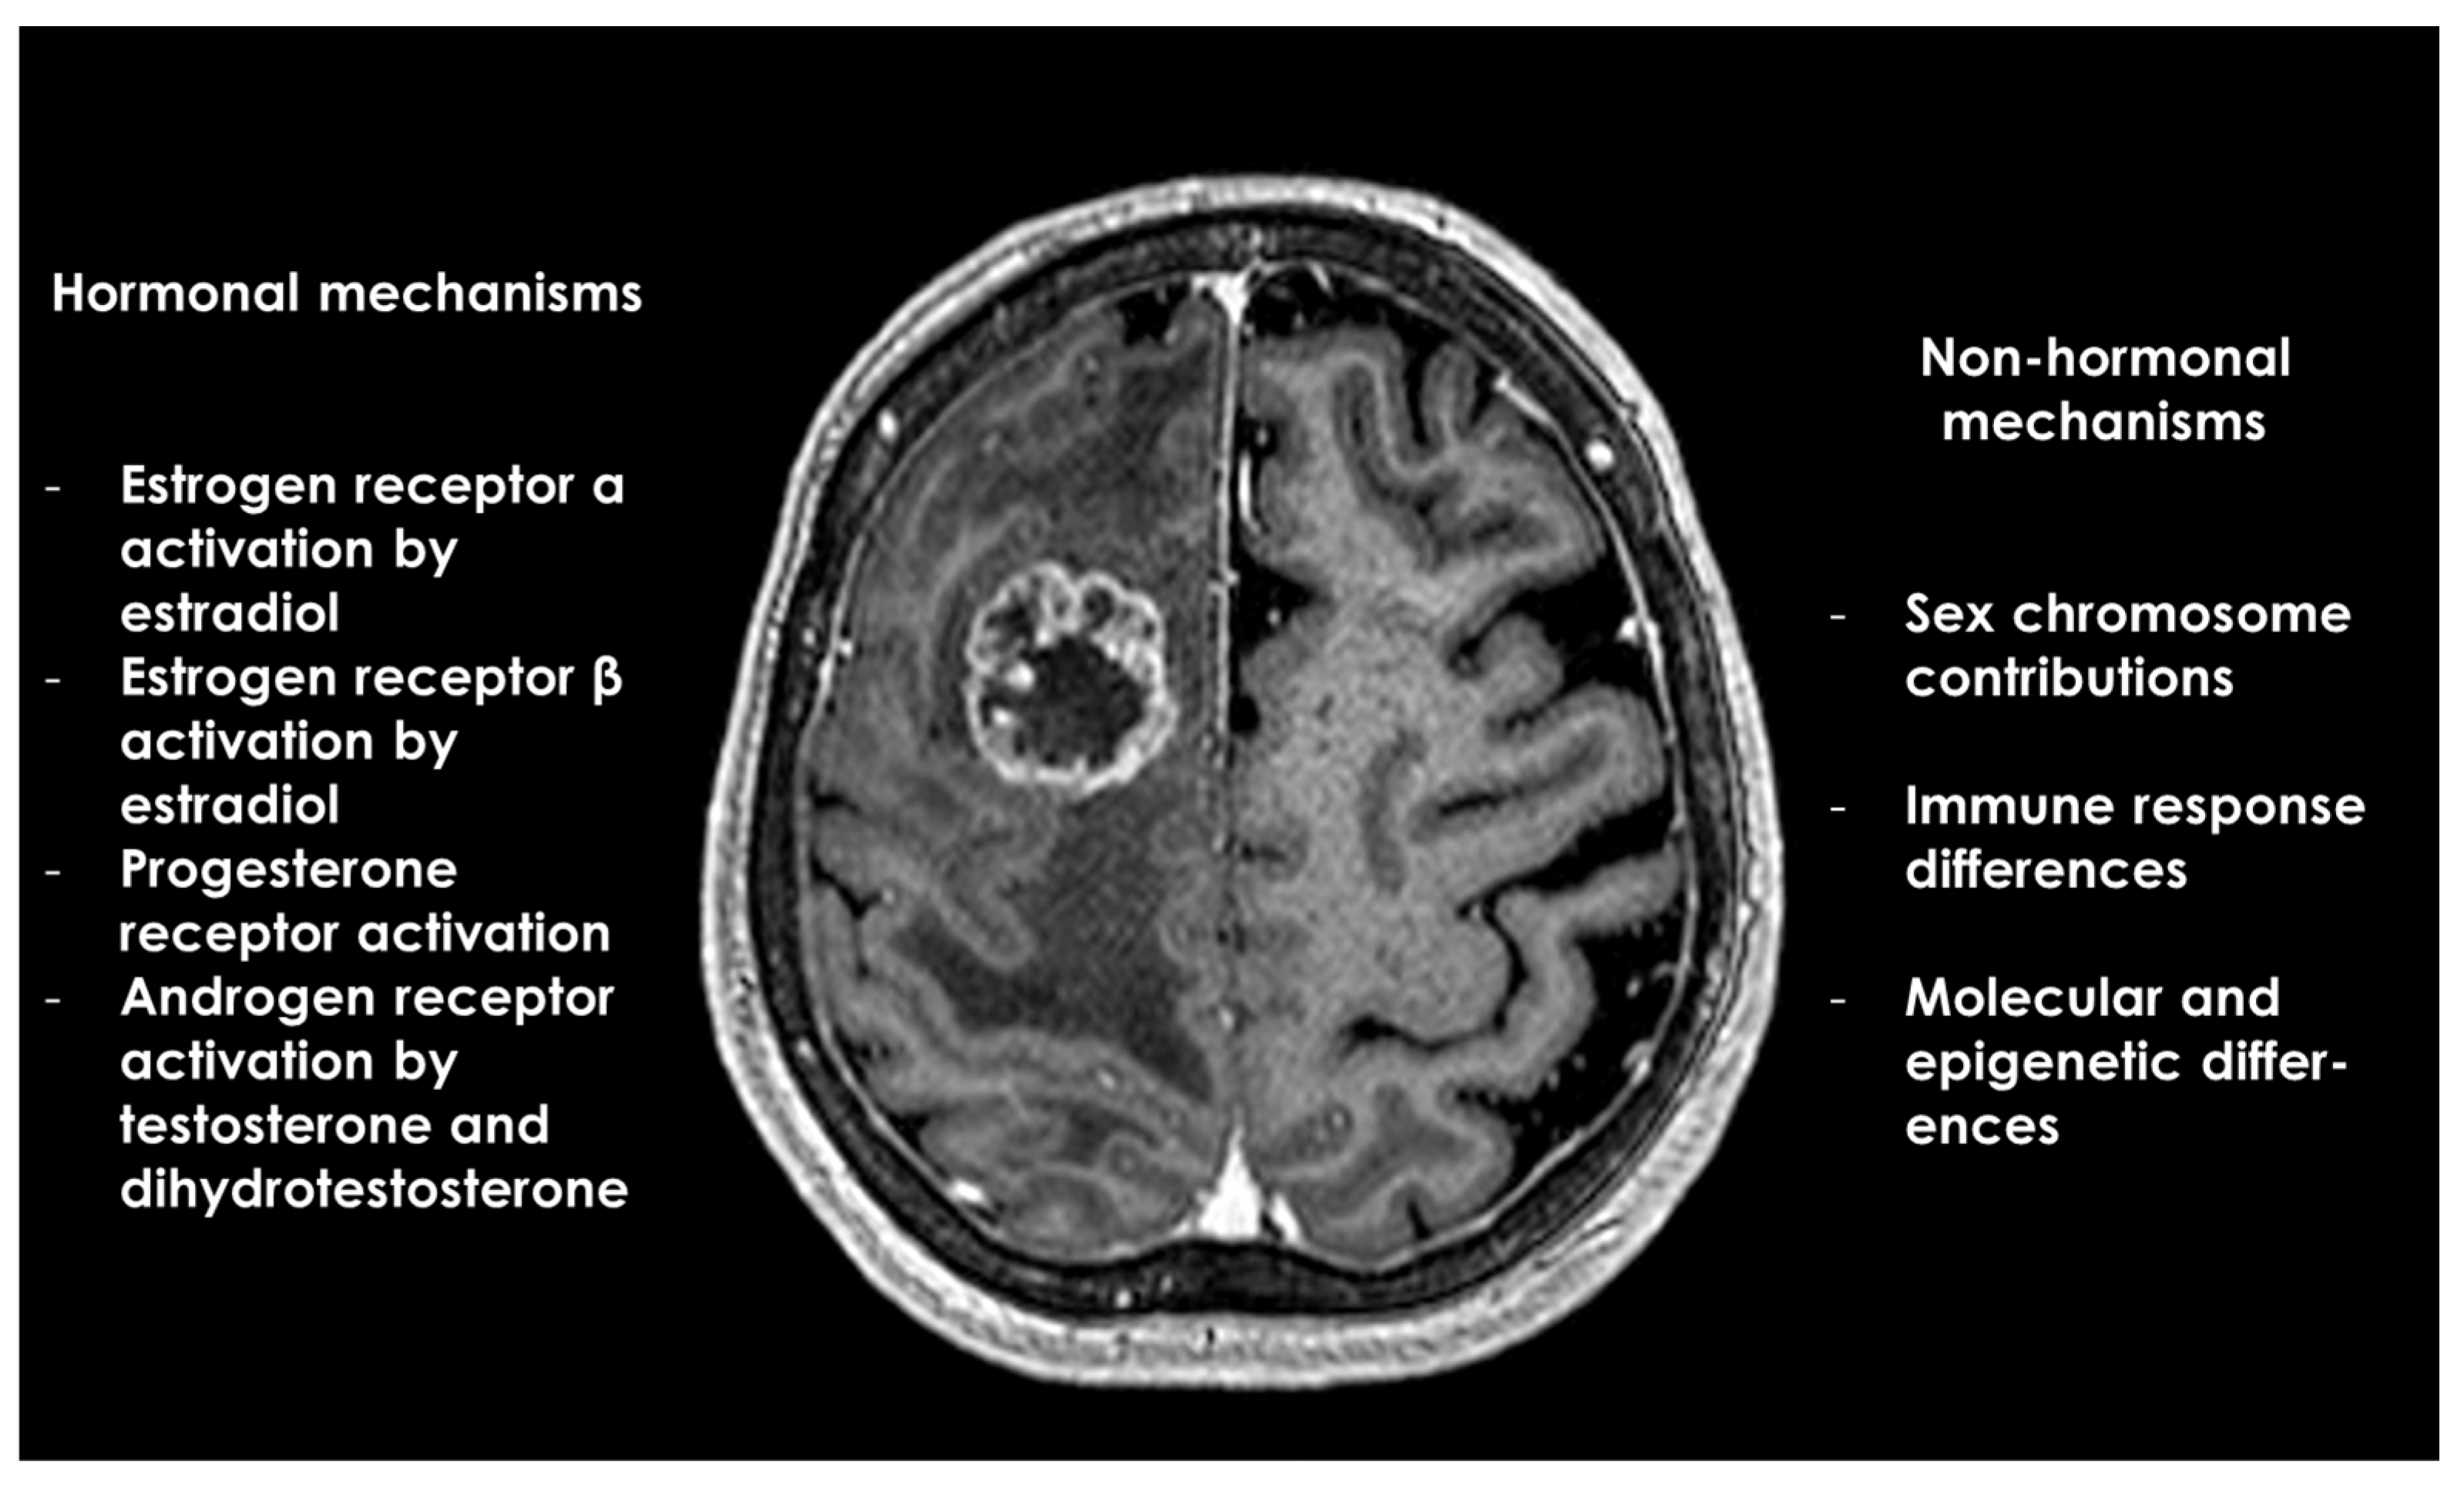

| Hormonal Mechanisms | Estrogen Receptor α Activation by Estradiol

| Progesterone Receptor Activation:

| Androgen Receptor Activation by Testosterone and Dihydrotestosterone (DHT): |

| Non-Hormonal Mechanisms | Sex Chromosome Contributions:

| Immune Response Differences:

| Molecular and Epigenetic Differences: